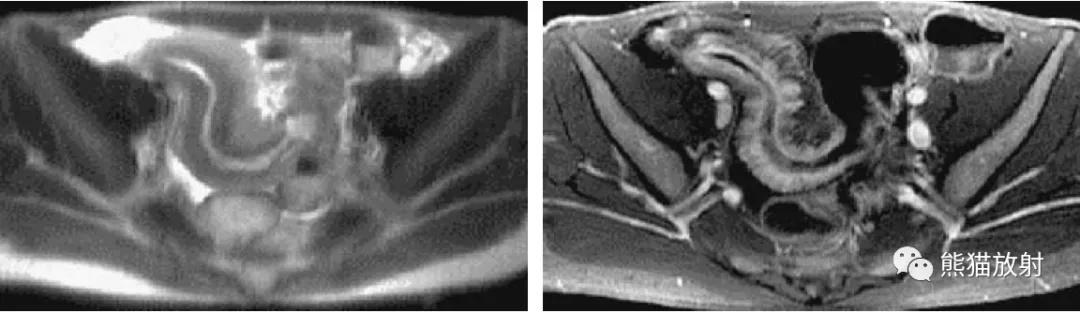

两张3D双对比MR虚拟结肠镜图像。可视化类似于使用CT获得的可视化